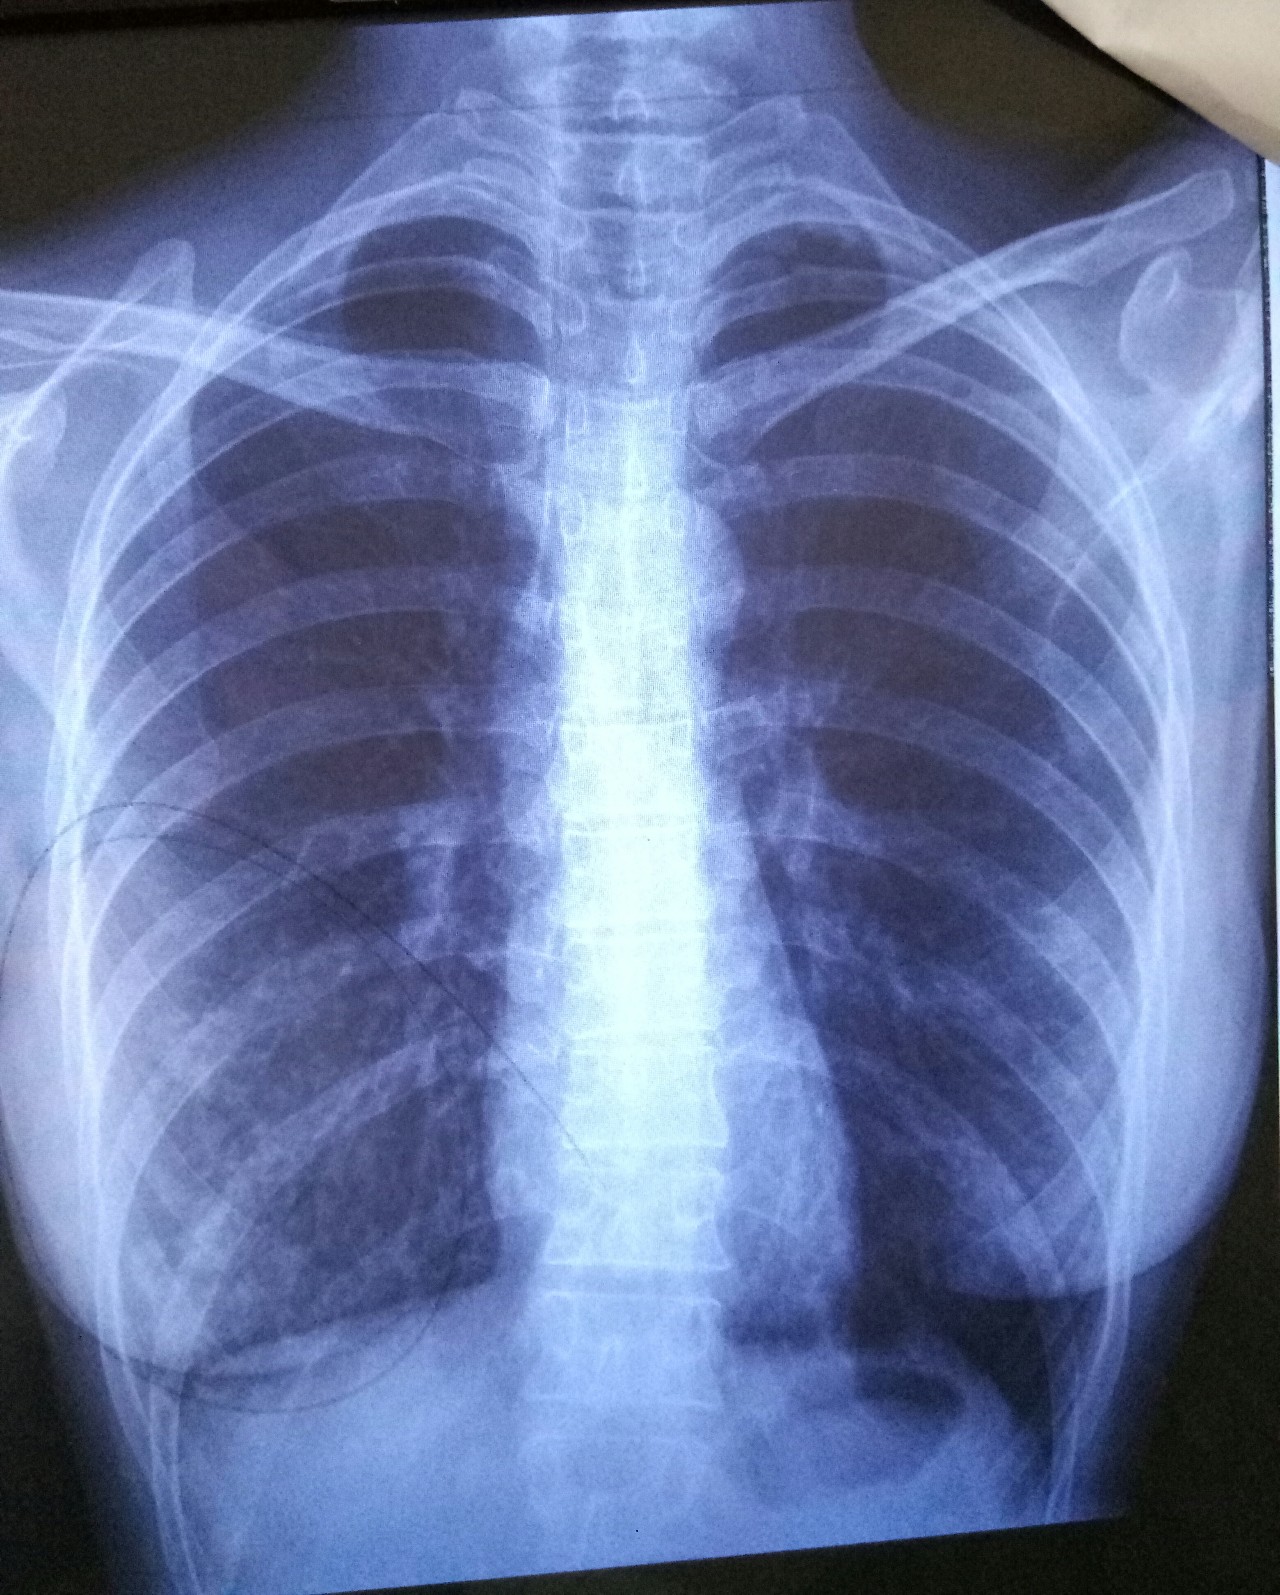

Рентгенография грудной клетки туберкулез

Рентгенография грудной клетки туберкулез

Туберкулёз лёгких на рентгене

Рентген грудной клетки туберкулез

Рентген грудной клетки туберкулез